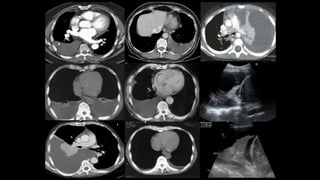

DIAGNOSTICO

Tomografia

Ultrassom